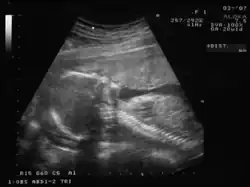

| Não invasivo | Ecografia obstétrica | Realizadas a partir da sétima semana para confirmar a gravidez e detetar a presença de gémeos. O exame da translucência nucal entre as 11 e as 13 semanas de gestação pode ser usado para identificar um risco acrescido de síndroma de Down. As ecografias morfológicas realizadas a partir da 18ª semana verificam qualquer desenvolvimento anormal. | Primeiro ou segundo trimestres |